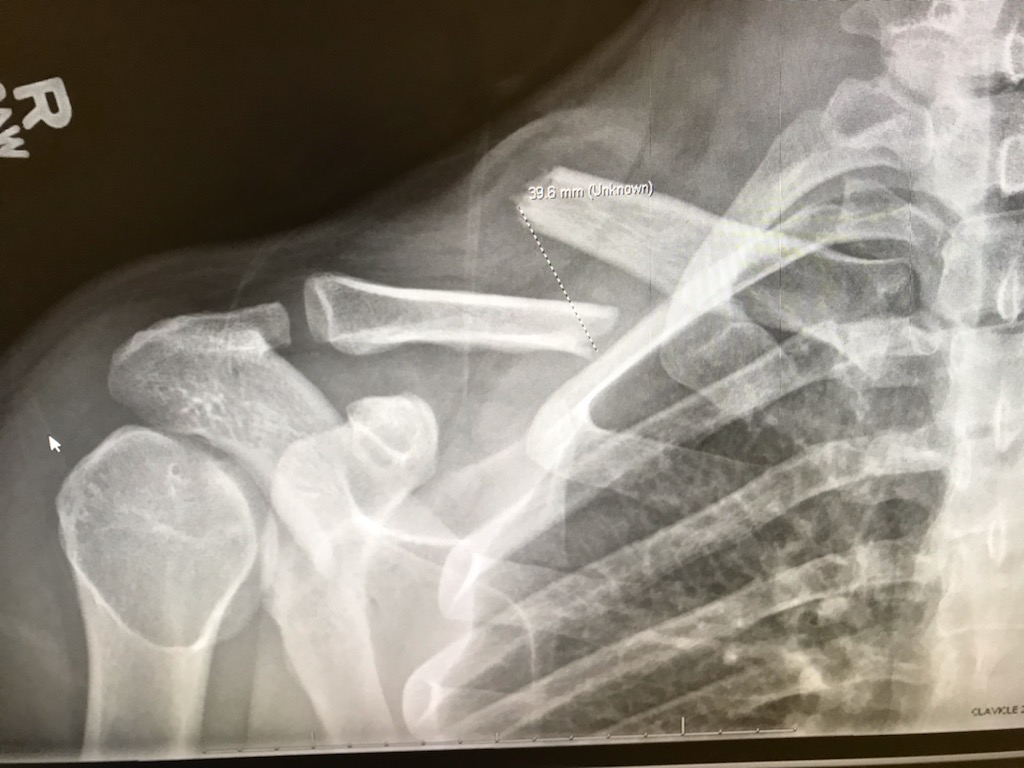

As of the time of writing, I have just been cleared for being out of a sling and returning to normal life after breaking my collarbone. It was my first bone breakage, and at this age, my first real contention with the biomechanical durability of the adult male structure. While a minimally impactful breakage (I healed really quick), it did make, and left plenty of time off for, reconsideration of my relation to recreational risk and the impact it can have on short term and long term physical abilities. I am blessed to have a job and life that does not strictly depend on my body, but this experience multiplied my appreciation for being able bodied, similar to how appreciative one feels of normal life while having the flu.